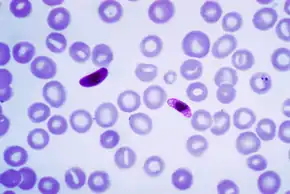

Malaria co-infection

Co-infection with hookworm and Plasmodium falciparum is common in Africa.[81] Although exact numbers are unknown, preliminary analyses estimate that as many as a quarter of African schoolchildren (17.8–32.1 million children aged 5–14 years) may be coincidentally at-risk of both P. falciparum and hookworm.[82] While original hypotheses stated that co-infection with multiple parasites would impair the host's immune response to a single parasite and increase susceptibility to clinical disease, studies have yielded contrasting results. For example, one study in Senegal showed that the risk of clinical malaria infection was increased in helminth-infected children in comparison to helminth-free children while other studies have failed to reproduce such results,[83] and even among laboratory mouse experiments the effect of helminths on malaria is variable.[84]

Some hypotheses and studies suggest that helminth infections may protect against cerebral malaria due to the possible modulation of pro-inflammatory and anti-inflammatory cytokines responses.[85] Furthermore, the mechanisms underlying this supposed increased susceptibility to disease are unknown. For example, helminth infections cause potent and highly polarized immune response characterized by increased T-helper cell type 2 (Th2) cytokine and Immunoglobulin E(IgE) production.[86] However, the effect of such responses on the human immune response is unknown. Additionally, both malaria and helminth infection can cause anemia, but the effect of co-infection and possible enhancement of anemia is poorly understood.[12]